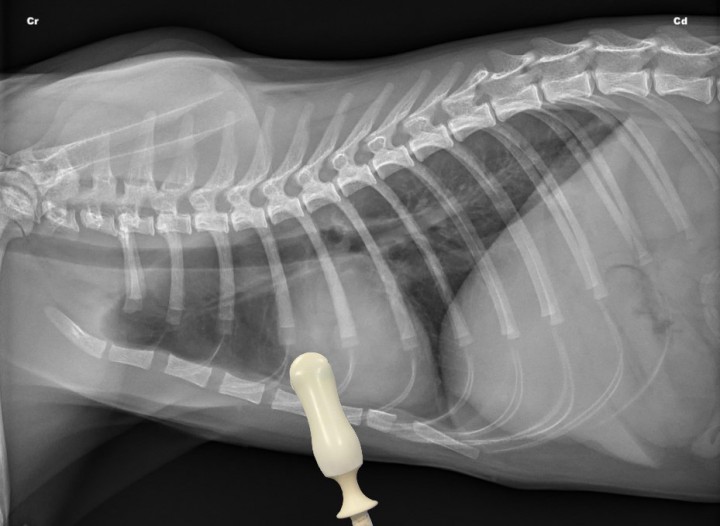

- Perihiliar (PH) bilateral (Fig. 2): Para la correcta valoración de este cuadrante, el transductor debe colocarse entre los espacios intercostales de la región perihiliar de ambos hemitórax y desplazarse entre ellos de forma dinámica. Se emplean para detectar la presencia de efusión pleural y pericárdica, así como valorar la volemia del paciente y descartar fallo cardíaco izquierdo mediante el ratio atrio izquierdo/aorta en el cuadrante PH derecho (menor a 1,6).[ Lisciandro G: Abdominal and thoracic focused assessment with sonography for trauma, triage, and monitoring in small animals. J Vet Emerg Crit Care 2011; 21(2): 104-122. [PubMed] , Boysen S, Lisciandro G: The Use of ultrasound for dogs and cats in the emergency room. AFAST and TFAST. Vet Clin Small Anim 2013; 43: 773-797. [PubMed] ]

<p>Radiografía lateral derecha de un gato sano en la que se observa la posición del transductor para valorar el cuadrante perihiliar (PH) de la T-FAST. Cr: craneal; Cd: caudal.</p>

Radiografía lateral derecha de un gato sano en la que se observa la posición del transductor para valorar el cuadrante perihiliar (PH) de la T-FAST. Cr: craneal; Cd: caudal.